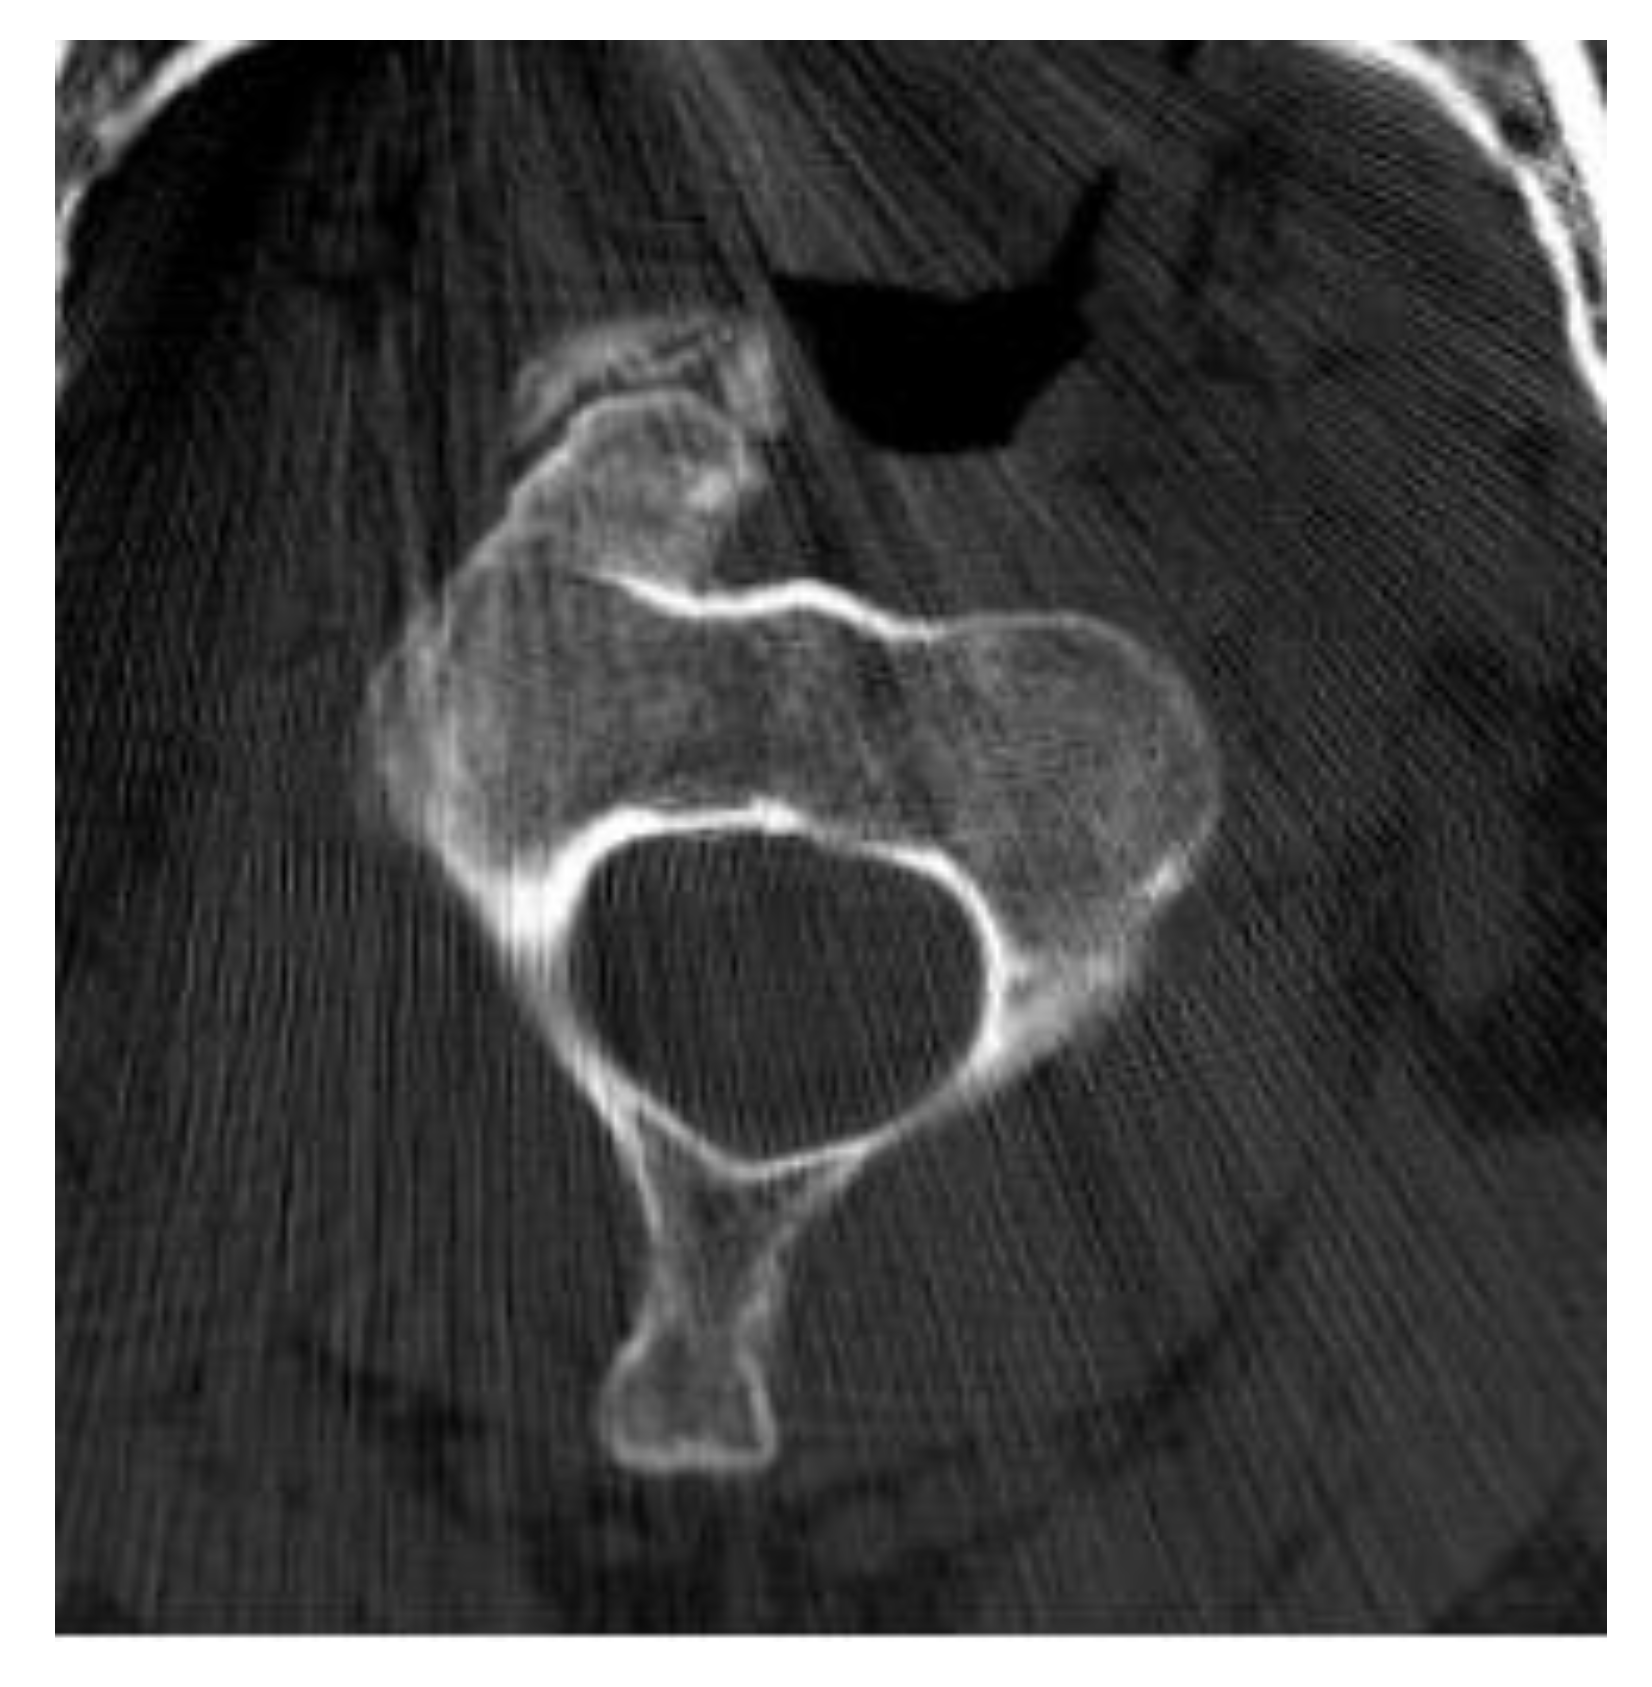

Aneurysmal Bone Cyst